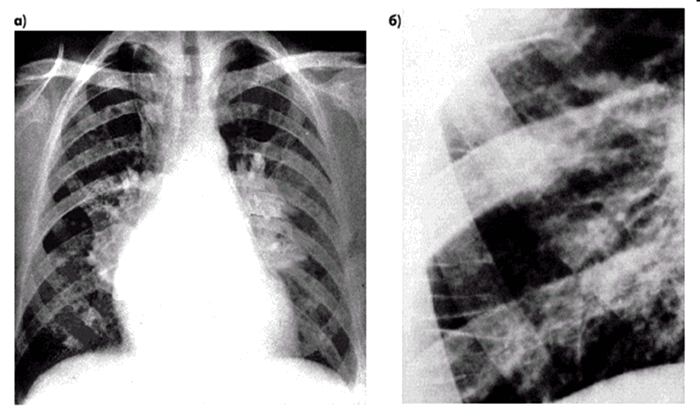

- R-графия легких: снижение прозрачности, субплевральный отек. «Крылья бабочки», диффузные или фокусные изменения;

3. Увеличенное давление наполнения левого желудочка. Застой в легких, подтвержденный клиническими данными (вновь возникшая одышка), или данными рентгенографии органов грудной клетки. Давление заклинивания легочных капилляров (именно так в первоисточнике), оцененное при катетеризации легочной артерии или путем допплерографии трансмитрального потока по данным эхокардиографии (ЭхоКГ) (время замедления волны «Е» не более 130 мс). Конечно-диастолическое давление в левом желудочке, измеренное при катетеризации, более 20 мм рт. ст.